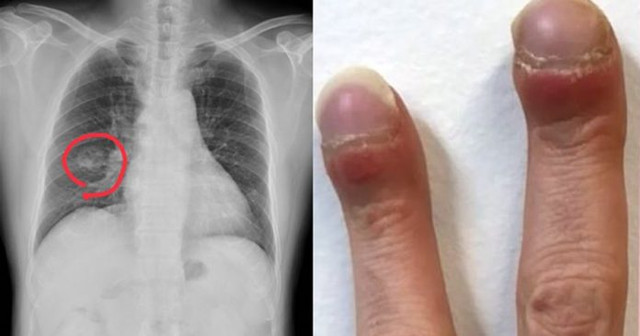

Bác sĩ Hồng chia sẻ hình ảnh về trường hợp bệnh.

Qua một thời gian, người phụ nữ phát hiện bàn tay mình có dấu hiệu lạ, thứ nhất là cơ ngay dưới ngón tay cái bị trũng xuống, thứ hai là ngón tay biến dạng, có hình dạng như dùi trống. Đồng thời, sức khoẻ ngày càng tồi tệ hơn.

Đi khám lại, bác sĩ Hồng quan sát tay của người phụ nữ và nhận thấy, chức năng tim phổi của bệnh nhân có vấn đề. Căn cứ vào hai biểu hiện bất thường trên, ông đề nghị bệnh nhân đi chụp X-quang và đo điện tâm đồ. Kết quả chẩn đoán là ung thư biểu mô tuyến ở phổi. Cũng may là giai đoạn đầu, vẫn còn kịp để chữa trị.

Qua trường hợp này, bác sĩ Hồng cũng nhắc nhở mọi người, khi ngón tay có thay đổi hình dạng bất thường, lòng bàn tay cũng có những dấu hiệu lạ, hãy đi khám ngay và lưu ý cho bác sĩ để được chẩn đoán nhanh, đúng, bắt kịp thời gian điều trị.